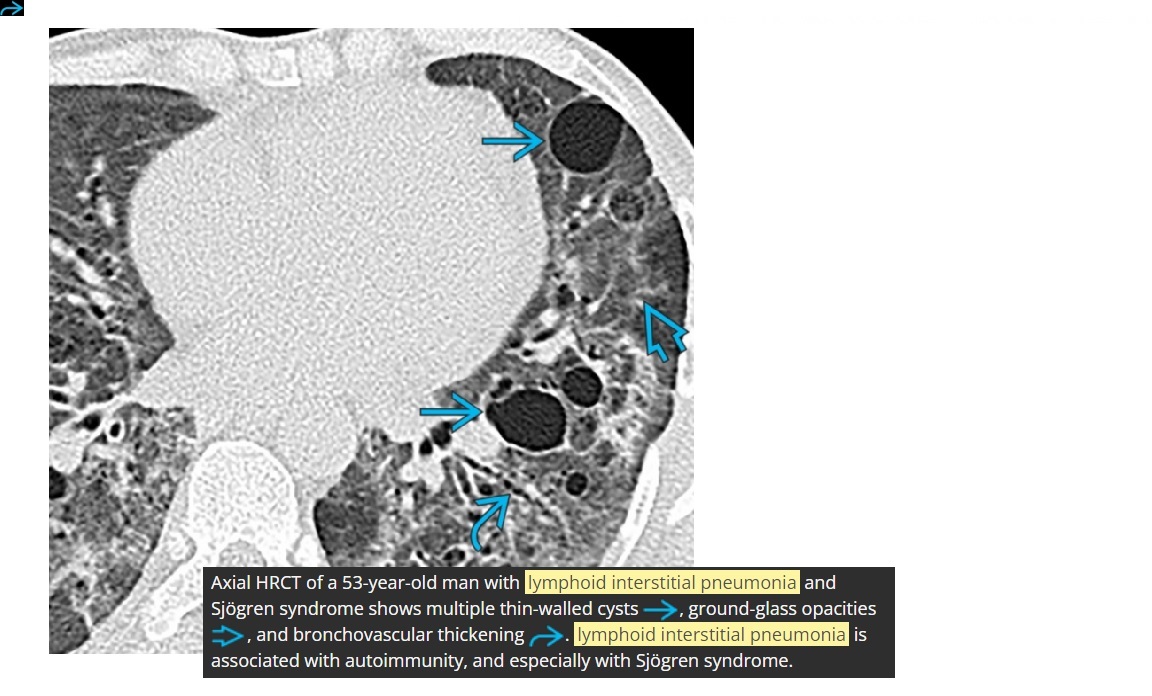

Lymphoid Interstitial Pneumonia - LIP

Basilar predominace

Thin walled cysts

GGO

Centilobualr micronodules

GGO clears with treatment

Associated with Sjogren’s

+ PCP, Hep B, EV

+ AIDs